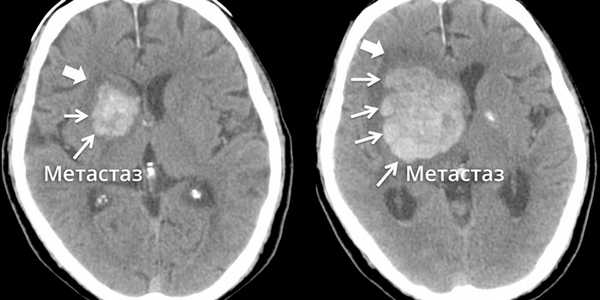

Как выглядят метастазы в головной мозг на компьютерной томографии (КТ)? Практически во всех случаях выявляется единичное (реже) либо множественные (чаще) объемные образования, которые отвечают следующим параметрам:

- Форма неправильная или сферическая

- Структура неоднородная, в центре очага может обнаруживаться область низкой плотности, обусловленная некрозом и распадом центральной части опухоли. По периферии — более плотный «ободок», который отражает активную часть опухоли, имеющую кровеносные сосуды и обладающую способностью к росту. Этот «ободок» окружен зоной низкой плотности, отражающей отек ткани мозга. Ширина данной зоны может быть различной — от нескольких мм до нескольких десятков см. Относительно однородная структура без наличия участка низкой плотности в центре и без перифокального отека. Такая структура метастаза свидетельствует о его относительной «доброкачественности»

- Отношение к прилежащим мозговым структурам. Очаги могут оказывать объемное воздействие различной степени выраженности на прилежащие отделы мозга, вызывая их смещение. Например, объемное образование в височной доле чаще всего приводит к выбуханию гиппокампа под намет мозжечка (височно-тенториальная дислокация), объемное образование мозжечка может воздействовать на мозговой ствол, приводя к его сдавлению, и т. д. Смерть при метастазах в мозг может наступить в результате сдавления мозгового ствола и нарушения дыхания и сердечной деятельности. В зависимости от локализации, вторичные очаги могут приводить к сдавлению церебральной ликворной системы, приводя к развитию окклюзионной гидроцефалии (резкому расширению центральных ликворных пространств на фоне повышения внутримозгового давления при окклюзии путей оттока ликвора из полости черепа)

- Тип роста. Метастазы могут обладать инфильтративным типом роста (расти, разрушая окружающие ткани) и экспансивным типом (расти, раздвигая окружающие ткани). В первом случае они чаще всего дают осложнения в виде кровоизлияния, то во втором обычно обуславливают возникновение дислокаций.

- Параметры контрастного усиления. Типичные вторичные опухоли в головном мозге увеличивают свою плотность в периферических отделах при внутривенном введении контраста, принимая вид «кольца», «полукольца», «спирали». Гораздо реже наблюдается равномерное контрастное усиление очага. Обычно центральная зона опухоли не усиливается, как и область перифокального отека.

Метастазы головного мозга, фото. На КТ с контрастным усилением у пожилой пациентки (в верхнем ряду слева) с жалобами на головные боли выявлены множественные объемные образования в левом полушарии мозга, интенсивно накапливающие контрастное вещество. Образования имеют характерную форму в виде «кольца». На изображениях в нижнем ряду и вверху справа определяются множественные очаги в головном мозге: отчетливо видны округлые образования с более плотным «ободком» по периферии, располагающиеся в левой теменной доле.